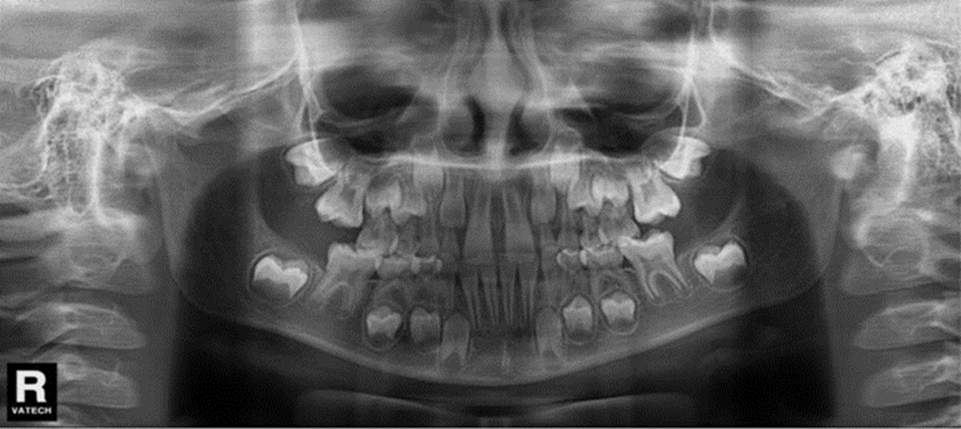

Autor: María Gabriela Flores Bracho. Fuente: Historia Clínica de M. C. M. H. 6 años. 04- 2010

Figura 5. Radiografía panorámica.